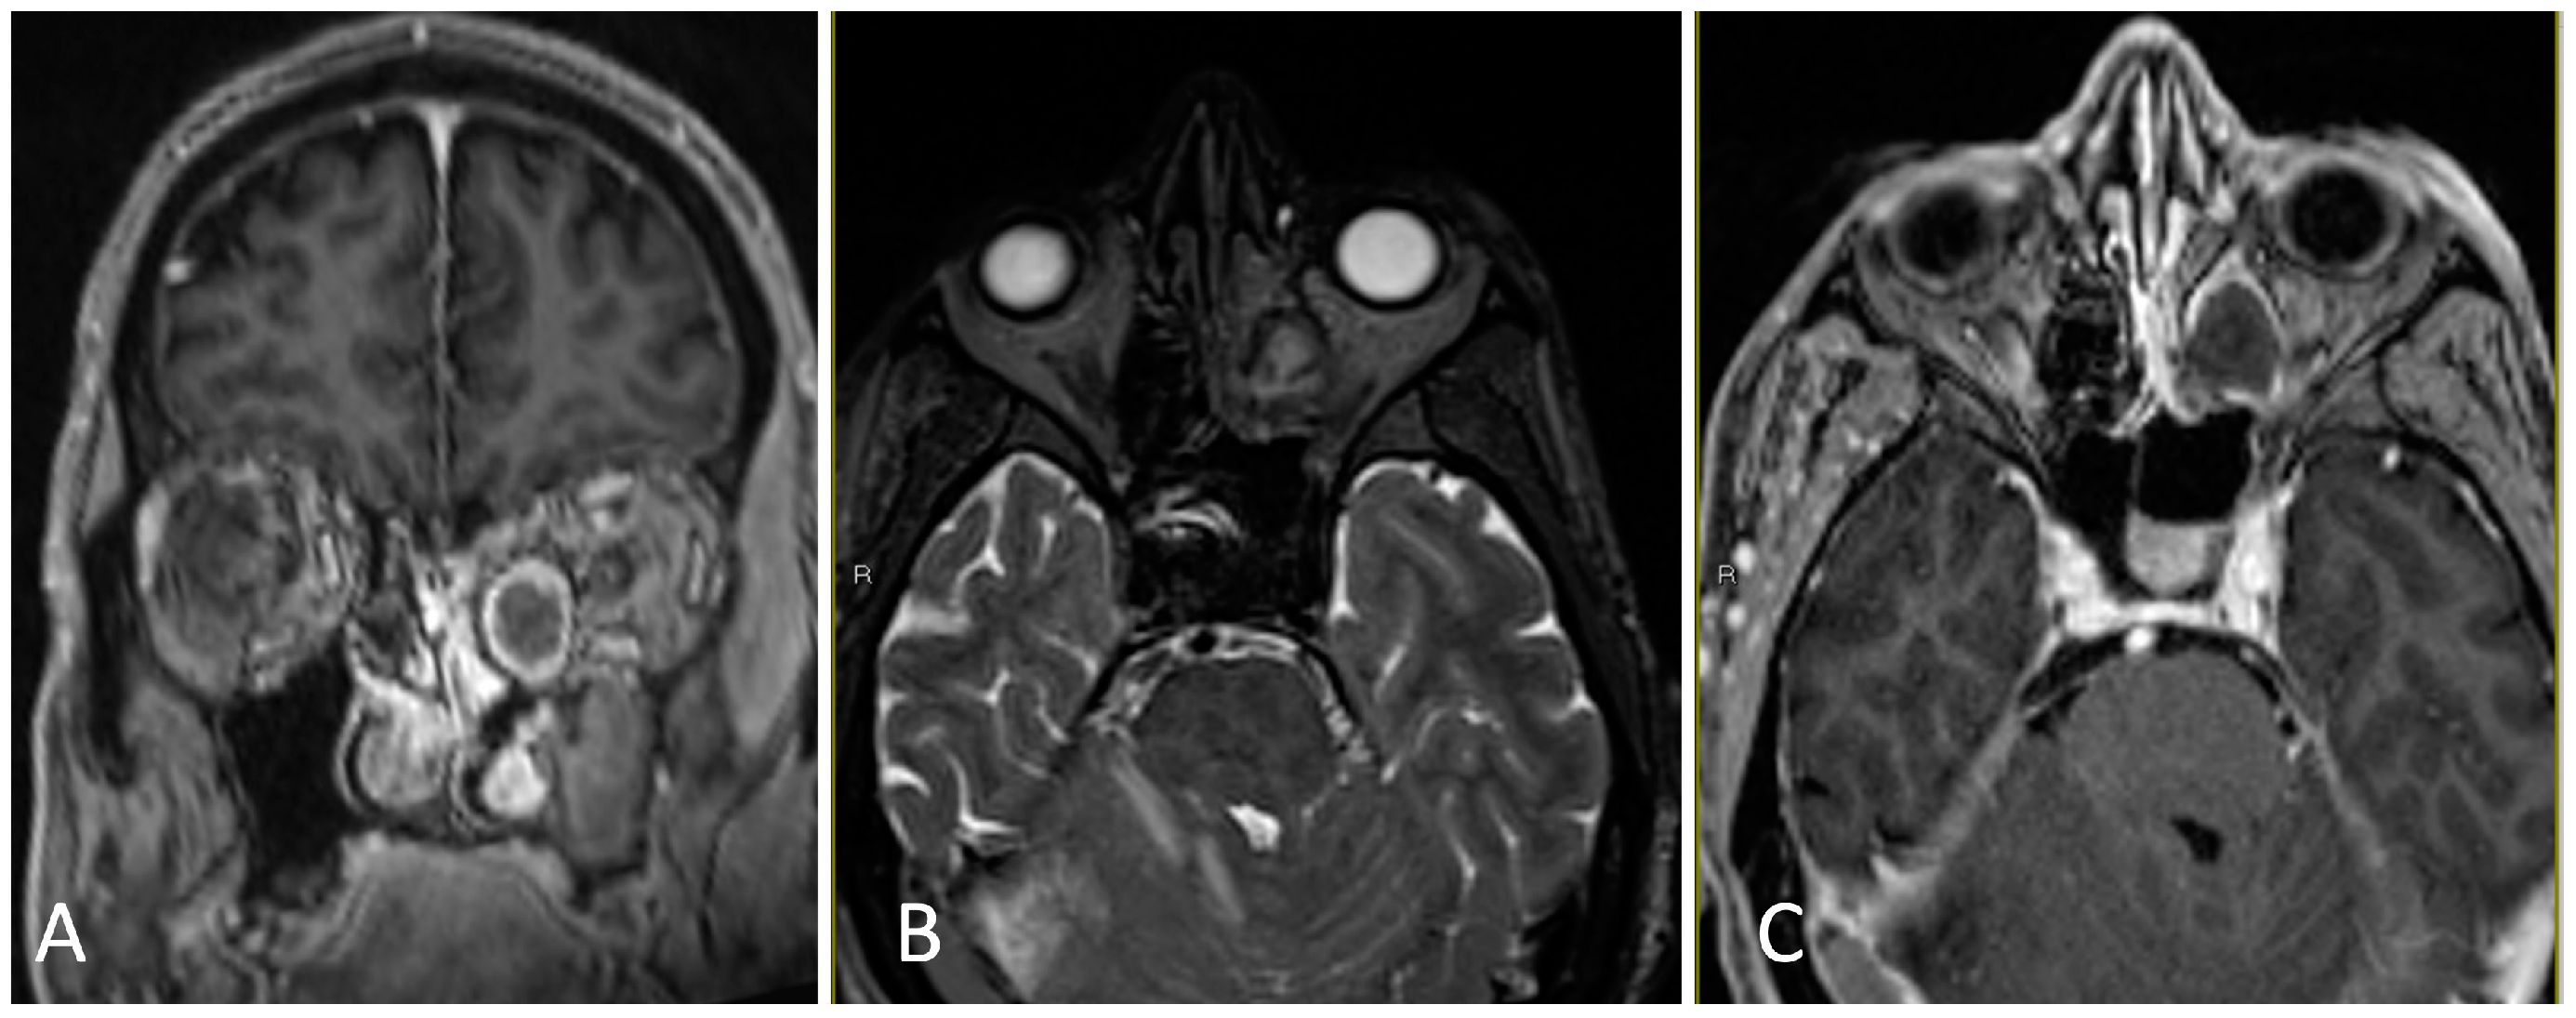

3.3.2. Illustrative Case

3.3.3. Practical Pearls

- Anterior and posterior ethmoidal arteries should be ligated and cut close to midline in order to avoid retraction of these vessels into the orbit.

- The inlay dural substitute should be oversized as part of the multi-layered closure.

- Reconstruction with a nasoseptal flap should take into account sites of involved disease, which cannot be used in the flap.